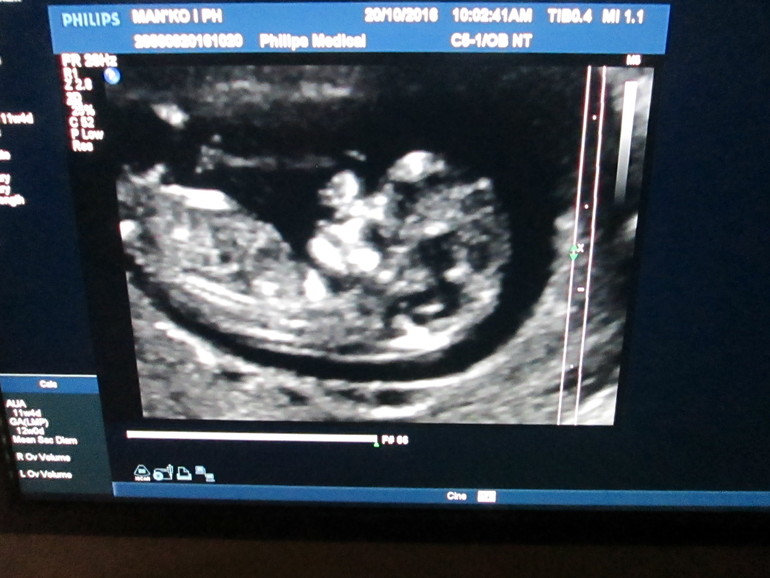

Сегодня сходила на узи посмотрела нашу крошку. Сегодня у нас 12 недель ровно, а по узи 11,5. Ничего страшного. Ктр 48 мм, ЧCC166, все остальные параметры в норме. Вообще прослезилась когда сердечко включили, волновалась как первый раз. Слава богу все хорошо. Всем счастья

И фото малыша снятое мною на телефон